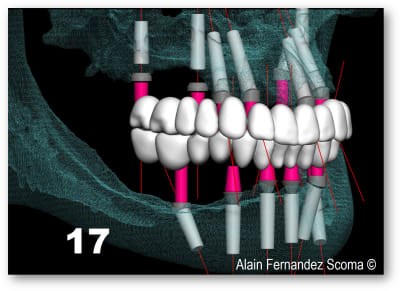

Olieve, un autre cas, patient de 24 ans maladie génétique entrai ant la perte de l'os médullaire, agénésie multiples ayant bénéficié d'un Leffort 1. Selon les critères que tu indiquais précédemment une MCI serait contre indiquée ?

voici ce qui a été fait par un chirurgien maxillo en AG qui avait à son actif une vingtaine d'implants posés, la S.I.A.O (17), pose des guides à appuis osseux (18, 19), résultat fin de chirurgie (20).